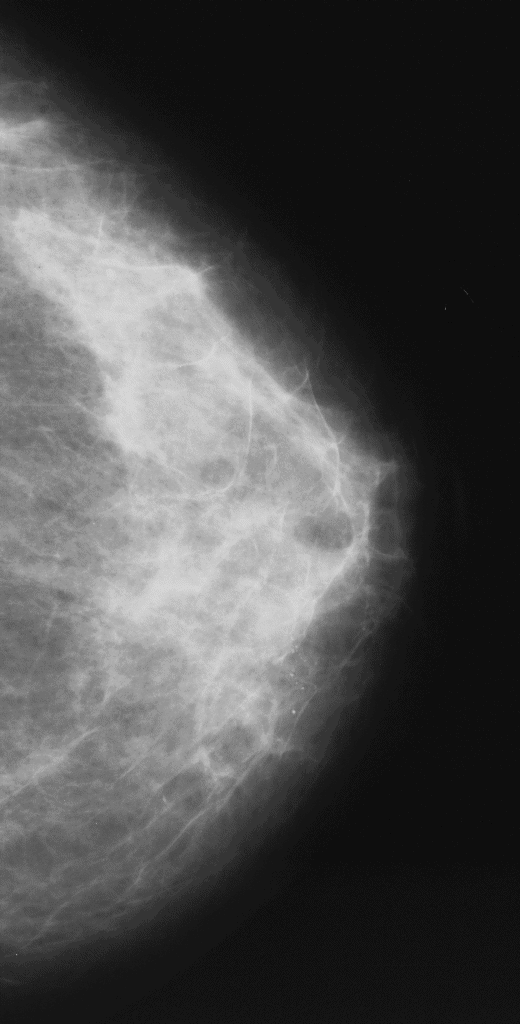

Mammografia con vista cranio-caudale